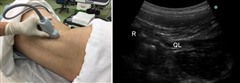

(3)ここで、腰方形筋を画像の中心に据えながら、プローブを回転させましょう。

これまでは、腰方形筋の横断面をみていましたが、縦断面がでるようにします。

うまく回転させないと、腰方形筋を見失ってしまうので気を付けてください。

末梢神経ブロック,神経ブロック,エコーガイド,動画,画像

このプローブの位置が、ちょうどL2の高さとなり、頭側の端に第12肋骨が見えます。